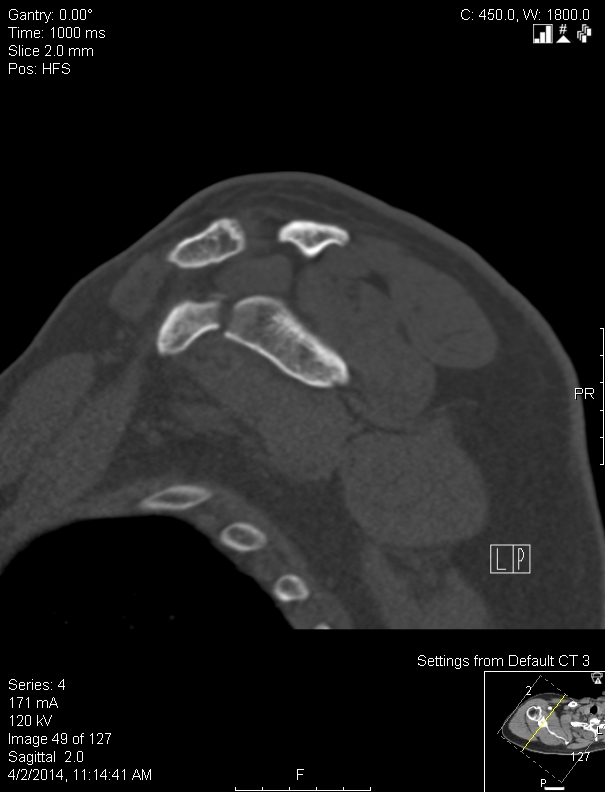

Scapula fracture causes, symptoms, diagnosis, treatment & prognosis

Comminuted Scapular Fracture Scapula Fracture Fixation Orthobullets generally speaking, fractures of the scapula heal at a faster rate than other fractures elsewhere in the body. for internal fixation of scapula neck fractures. A fairly limited approach to the shoulder, allowing little anterior exposure. scapula fractures are uncommon fractures to the shoulder girdle caused by high energy trauma and. The actual fracture typically heals within. Scapula Fracture Fixation Orthobullets.